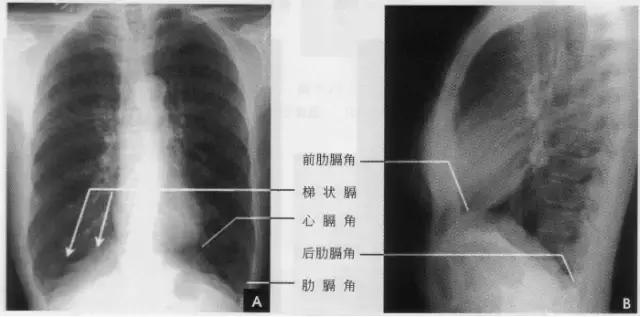

五、膈

隔为一薄层肌腱组织,位于胸腔和腹腔之间,分左右两叶,各呈圆顶状,其上、下面分别为胸、腹膜昕覆盖。膈上各肌束之间有三角形裂隙,有数孔道供贯通胸腹腔的结构经过,其三角区和孔道均构吱横瞒的生理薄弱点,是膈疝的好发部位。膈肌的运动是呼吸动作的重要部分,占肺活量的60%。膈吼收缩时,圆顶减小并降低;弛缓时,圆顶抬高。膈的运动幅度在平静呼吸时为1~3cm,深呼吸时为1~5 cm。两膈的活动度大致对称。

在正位胸片上,膈显示为圆顶状阴影,边缘光滑整齐,顶峰靠近中内1/3处。内侧与心脏形成心膈角。外侧与胸壁相交形成肋膈角;在侧位片上,圆顶部靠前,前端与前胸壁形成前肋膈角,后部与后胸壁形成后肋膈角,正常时前、后肋膈角均为锐角,后肋膈角位置最低。右膈顶的位置,一般与第6前肋或第10后肋等高,多数人右膈比左膈高1~2cm,这是因为心脏位置偏于胸腔左侧,故而将左膈压低。膈的位置在正常时可有若干变动:例如儿童膈位置较高,老年人则较低;矮胖型膈位置较高,瘦长型则较低;卧位时膈位置较高,立位时则较低;呼气时膈位置较高,吸气时则较低等。

膈形态的变异有:

①局限性瞒膨出:系蕊部分肌纤维短而薄弱引起张力不匀所致。

②波浪瞒:在深吸气时膈面呈3~4个小弧形隆起影,边缘部相互重叠。这是由于膈个别肌束肥大引起其收缩不均匀所致。

③梯状膈。深吸气时膈面出现数个呈梯状排列、尖端引向外上方的突起影,这是由于附着于各前肋端的膈面被肋骨过度牵引所致(如下图)。